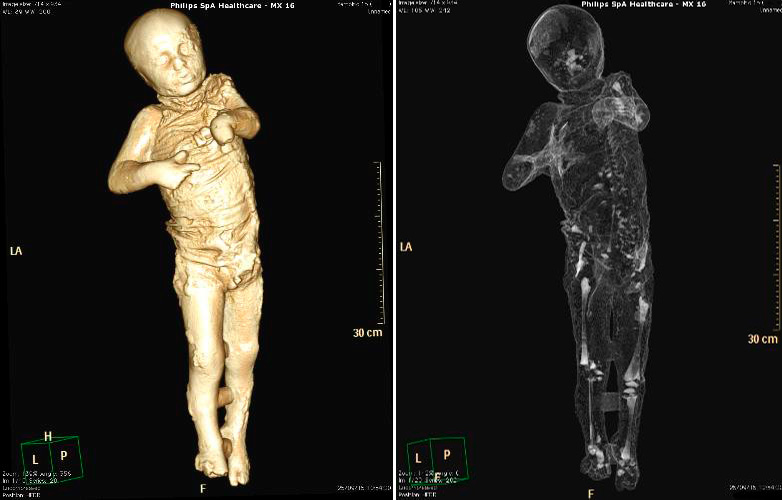

Por primera vez, un grupo de moldes de yeso de Pompeya ha sido sometido a tomografías axiales computerizadas (TAC), a partir de las que ha sido posible determinar la edad, las patologías médicas, los hábitos alimentarios y el estilo de vida de los habitantes de la ciudad arrasada por el Vesubio en el 79 d.C.

El objetivo del estudio radiológico ha sido obtener imágenes del interior de los cuerpos que quedaron conservados en ceniza durante la erupción del volcán, y que luego fueron rellenados con yeso con el propósito de preservar su integridad.

Asimismo, han sido realizados relieves en tres dimensiones de todos los cuerpos mediante técnicas digitales de vanguardia que permiten obtener datos sobre cómo ha variado su estado de conservación en el tiempo.